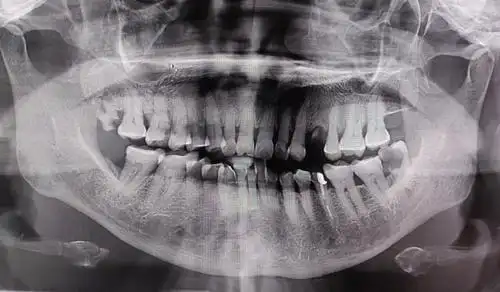

慢性根尖周炎急性发作一例-医联

上前牙窦道型慢性根尖周炎一例

根尖处这样大的阴影《附牙片》要怎么处理最好!

赶紧跑去口腔医院,做了检查,拍了片,诊断是慢性根尖周炎,其实这颗牙齿

慢性牙周炎根尖图片